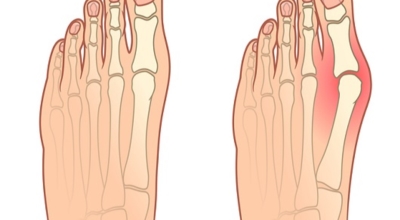

3. 엄지발가락 통증 - 무지외반증

우리에게 잘 알려져 있는 엄지발가락 통증의 원입니다. 선천적 요인으로 인한 발병보다는 하이힐, 뾰족구두, 키높이 깔창과 같이 앞이 좁고 엄지발가락에 자극이 심한 신발 유행으로 후천성 환자가 늘어나고 있습니다. 체중 증가나 류마티스 관절염도 무지외반증의 원인입니다. 엄지발가락이 둘째 발가락으로 휘어지면서 대측으로 회전해서 제1중족 관절이 안쪽으로 돌출되는 무지외반증은 서있거나 걸어 다닐때 신발과 마찰해 통증과 염증이 발생합니다.